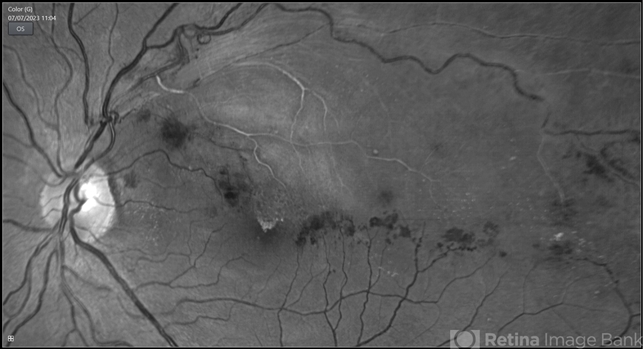

- BRVO

- BRVO, branch retinal vein occlusion (BRVO), non-perfused branch retinal vein occlusion (BRVO)

- 43-year-old woman presented with left eye old STBRVO with chronic CME of duration 6month showing ring shaped collaterals more evident on red free image